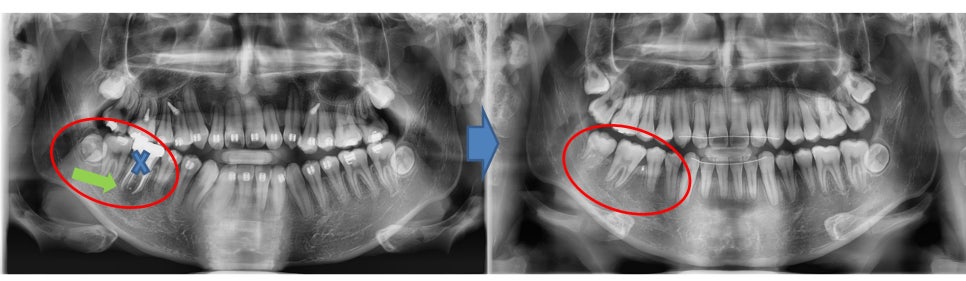

¾Æ·¡ ¾î±Ý´Ï¿¡ ¹®Á¦°¡ »ý°Ü¼­

Ä¡·á¸¦ Çϱ⠽±Áö ¾Ê¾Æº¸¿©

¹ßÄ¡Çϰí

½Ã°£ÀÌ Á» °É¸®´õ¶óµµ

µÚÀÇ »ç¶û´Ï¸¦ ¾ÕÀ¸·Î ´ç±â´Â Á¶Ä¡¸¦ Çϱâ·Î

ÇÏ¿´½À´Ï´Ù.

¿À¸¥ÂÊ ¾Æ·¡ ¾î±Ý´Ï¸¦ ¹ßÄ¡ÇÏ¿´°í

¹ßÄ¡ °ø°£ ÀüÈÄÀÇ Ä¡¾Æ¸¦ ¿òÁ÷¿©

°ø°£À» ¾ø¾Ö±â·Î ÇÏ¿´½À´Ï´Ù.

¾î±Ý´Ï¸¦ ¹ßÄ¡ÇÏ¿´°í

»ç¶û´Ï°¡ ¾ÆÁ÷ ¸Ó¸® ¹Û¿¡

Çü¼ºÀÌ ¾ÈµÈ »óÅ¿´Áö¸¸

»Ñ¸®°¡ Àß ¹ßÀ°µÇ¸é¼­

Á¤»óÀûÀ¸·Î

¾î±Ý´Ï ¿ªÇÒÀ» ÇÒ ¼ö ÀÖ°Ô µÈ °ÍÀ» º¼ ¼ö ÀÖ½À´Ï´Ù.